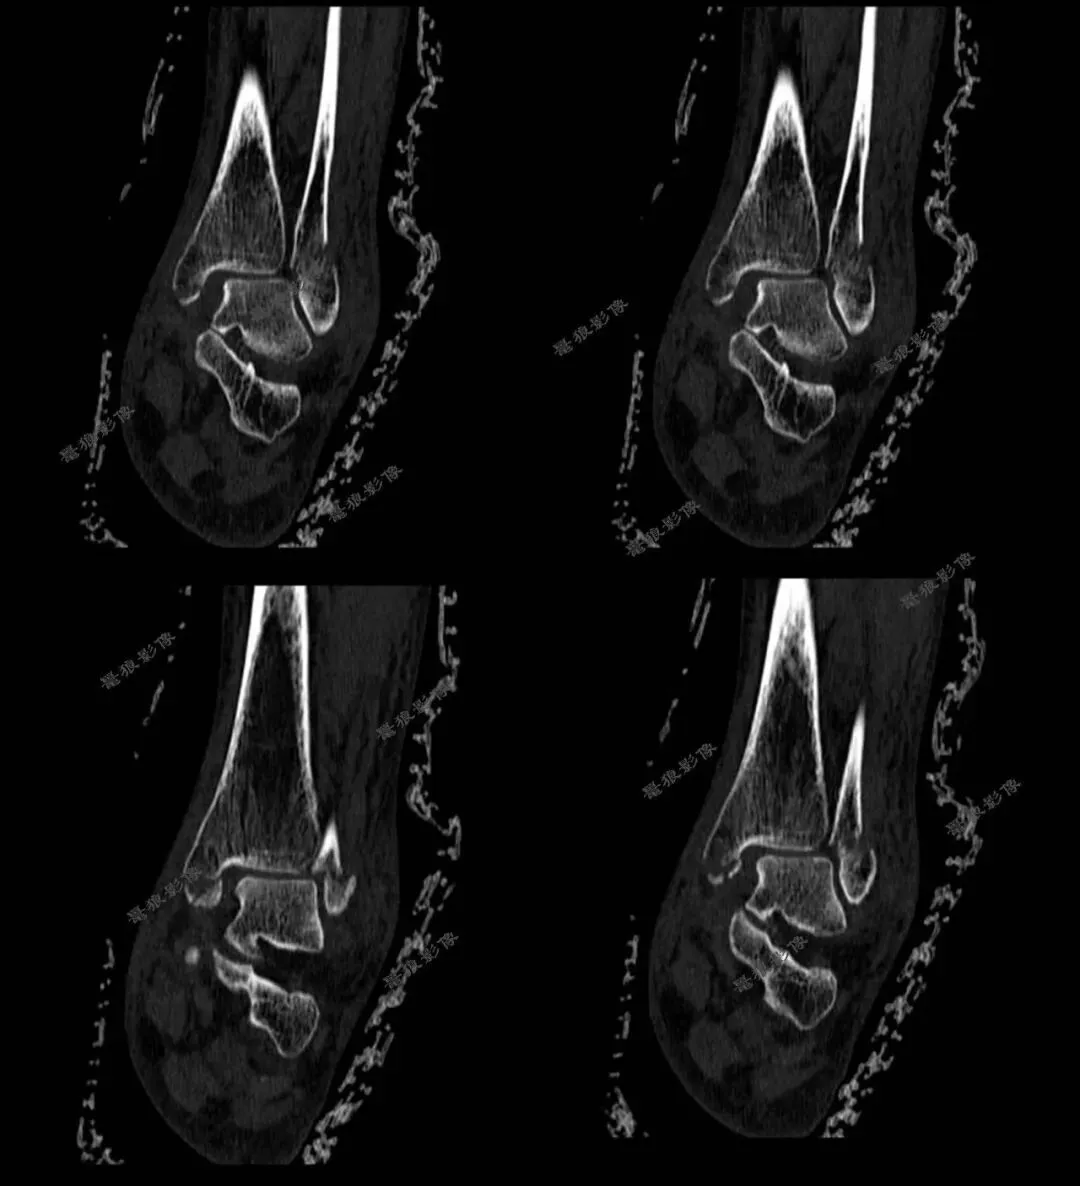

F,62y。跌伤左踝部肿痛活动受限3小时余。

术前CT:

1、左三踝粉碎性骨折,胫距关节半脱位,踝关节软组织肿胀;

2、左足舟状骨、内侧楔骨、第1-4跖骨近端骨折。